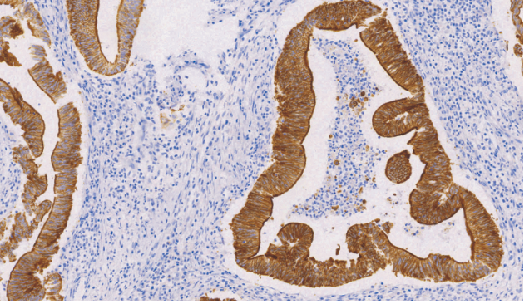

Villin鼠抗人绒毛蛋白单克隆抗体

Villin与结构相关蛋白凝溶胶蛋白(gelsolin)、片段化蛋白(fragmin)及割切蛋白(sevenrin),全部参与肌动蛋白(actin)的框架调节与装配正常分布于肠上皮和肾近小管上皮,可用于肠上皮来源肿瘤与非肠上皮肿瘤的鉴别诊断,亦可作为胃肠道神经内分泌肿瘤诊断参考指标。

- 阳性部位:胞质,胞膜